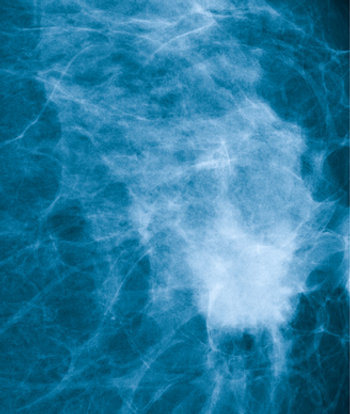

Ultrasound proved better than tomosynthesis at finding breast cancer in women with dense breasts where mammography had not detected any cancer.

Clear guidelines about the utilization of MRI in breast cancer detection and management are needed, as the modality is being overused in women for whom it offers few benefits (and potential harms), and underused when it might be appropriate.

A study including nearly 30,000 women found that newly diagnosed early-stage breast cancer patients often undergo advanced imaging tests, in spite of recommendations against this practice.